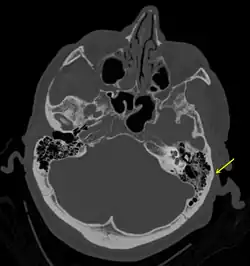

| A subtle temporal bone fracture as seen on a CT scan | |